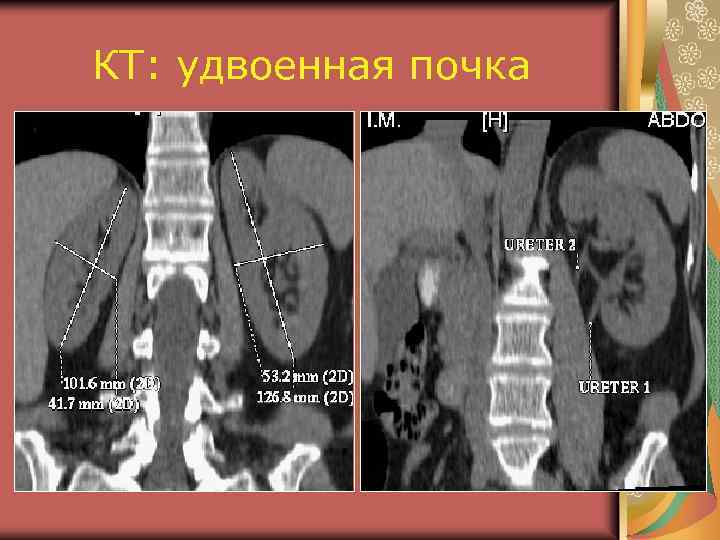

КТ: удвоенная почка